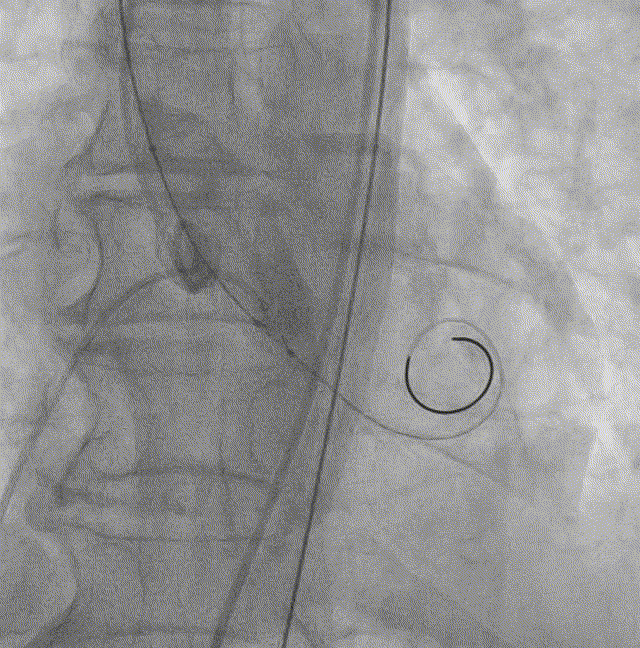

主动脉瓣CT评估:三叶瓣,双冠脉开口水平可,钙化分布较均匀。双侧髂股动脉内径可。瓣环长短径分别为17.9*25.1mm,周长为68.8mm,面积为358.1mm²。

瓣上多平面测量:

主动脉根部整体形态(自流出道至升主动脉方向):

瓣叶运动4DCT:

血管入路评估: